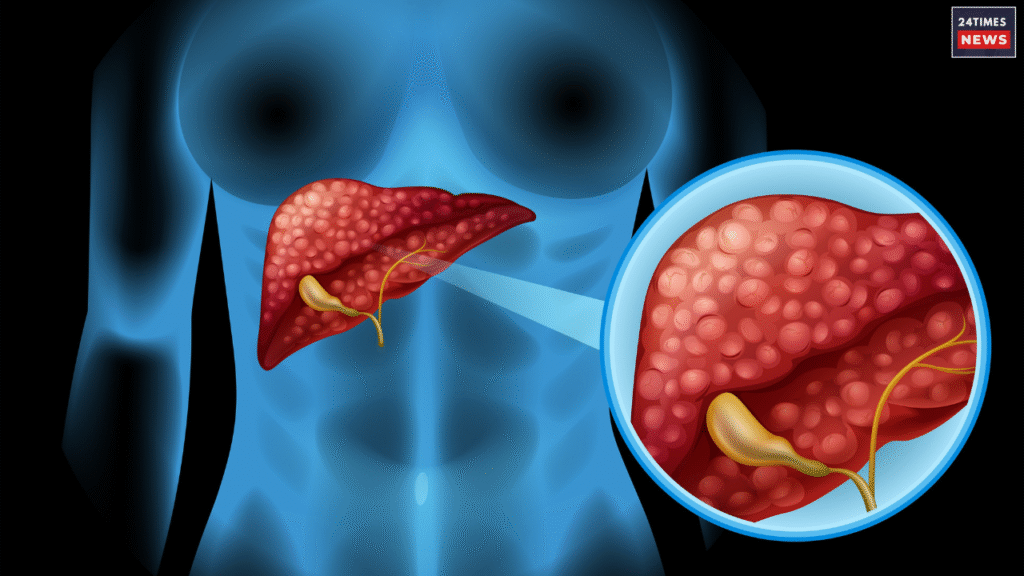

The liver does more than just detox the body-it performs over 500 important functions. It helps purify the blood, strengthens digestion, controls the hormones, stores energy, and removes the toxins. If the liver stops the working properly, toxins start building up in the body, leading to various diseases. eating too much oily foods, drinking alcohol, lack of proper sleep, and high stress can all harm the liver health. These habits can increase the risk of fatty liver, liver inflammation, or excess heat in the liver. When the heat in the liver rises, the body begins to show certain symptoms such as fatigue, skin problems and poor digestion. Fatigue, skin problems and poor digestion. Maintaining the healthy lifestyle and diet is essential to keep the liver cool and functioning well, as it plays a key role in keeping the entire body healthy.

When heat in the liver increases, its effects can easily be seen on the mouth and skin. frequent mouth ulcers, burning sensation in the tongue or mouth, and skin rashes or itching are common signs of liver heat. it can also affect your mood, causing the frequent anger, irritation or restlessness. liver heat doesn’t just stop there- it impacts digestion as well. Many people experience indigestion, acidity or a burning feeling in the stomach when the liver becomes overheated. These are warning signs that your liver may be under stress and needs care. staying hydrated, eating light and balanced meals, and avoiding spicy or oily foods can help reduce liver heat. Managing stress and getting proper sleep are equally important to keep the liver healthy and maintain overall body balance.

How to Reduce the Heat of the Liver?

If you have the fatty liver, it’s important to take care of your oral health too, as liver problems can affect your mouth and teeth. Brush your teeth twice a day-morning and night and use floss regularly to prevent decay and bacterial growth in the gums. Get your teeth checked from time to time to detect any issues early. Include healthy foods in your diet such as fresh fruits, green vegetables and protein-rich items to support liver function. Drink plenty of water throughout the day to cool down the stomach and liver naturally. Avoid fried foods, alcohol and junk food completely, as they increase the liver heat and toxins in the body. Following a clean diet and maintaining good hygiene can help keep your liver healthy and your overall system balanced.